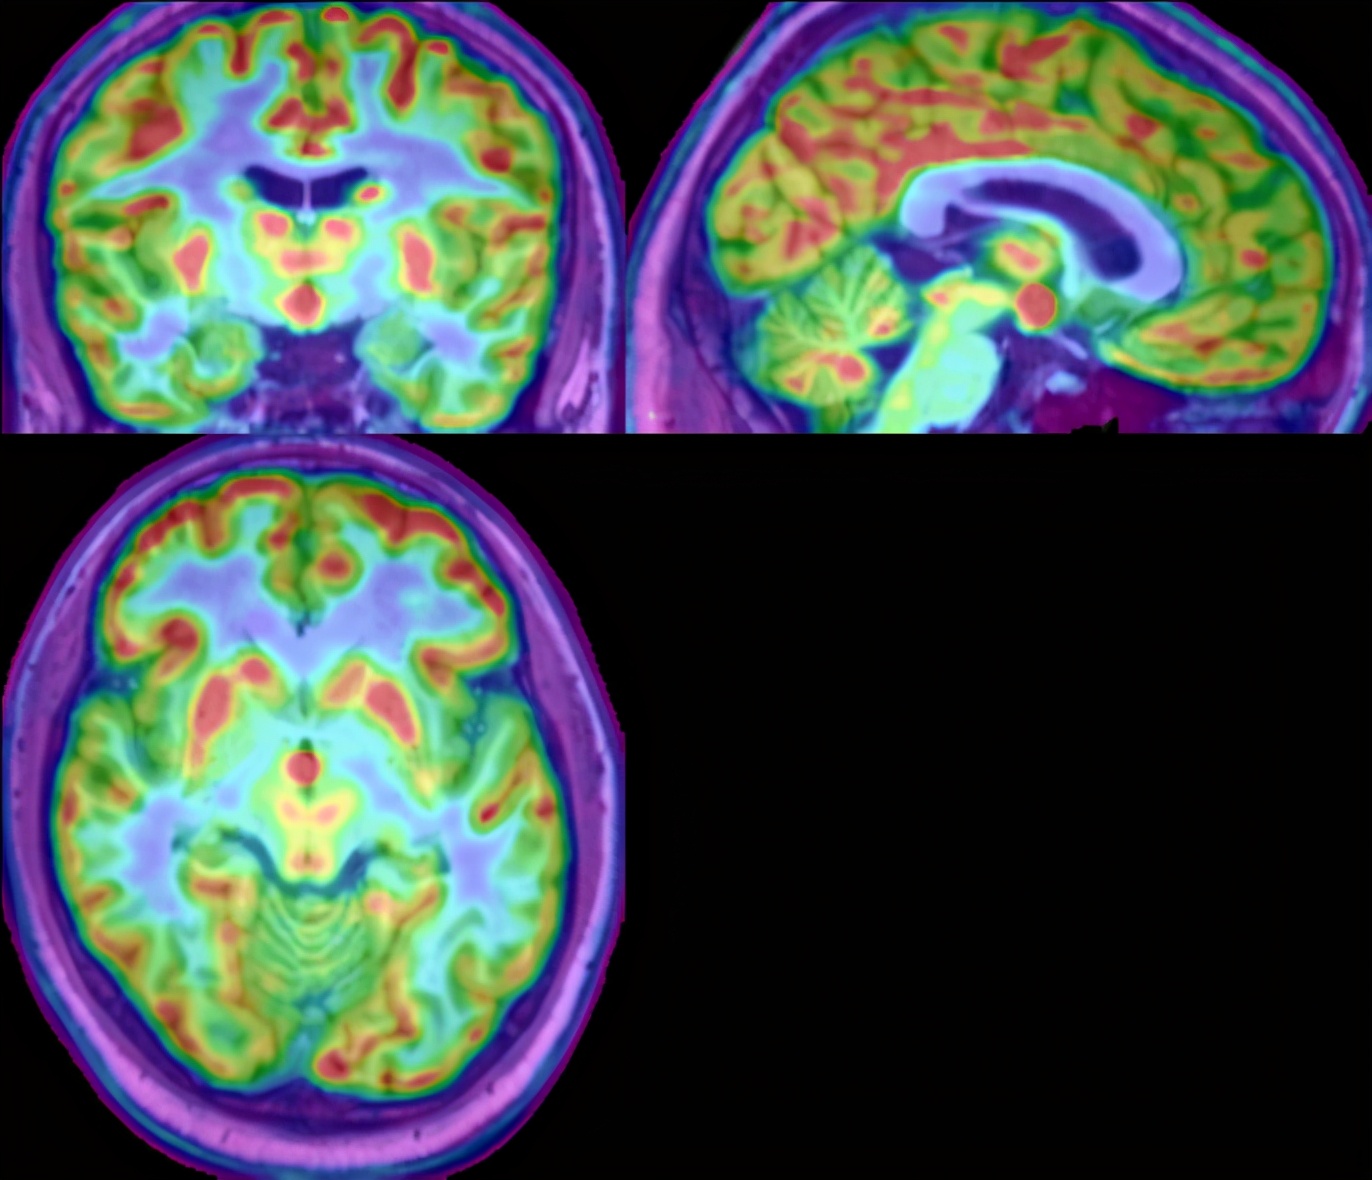

小天入院后进行了长程视频脑电图监测、等体素MRI及PET-CT等全面系统的检查,同时利用目前最先进的影像后处理技术将MRI与PET-CT进行融合,发现了位于下丘脑直径7毫米的错构瘤。哈医大二院神经内科教研室主任、癫痫中心主任朱雨岚教授邀请了包括儿科郝艳秋教授,PET-CT主任李萍教授,神经外科孙家行主任医师,核磁共振程义鹏副主任医师在内的多学科专家为小天进行仔细规范的术前评估。结合患者的症状以及对影像的精准判断,最终确诊是由下丘脑错构瘤导致的痴笑发作。

PET-CT与MRI影像融合捕获痴笑“真凶”下丘脑错构瘤